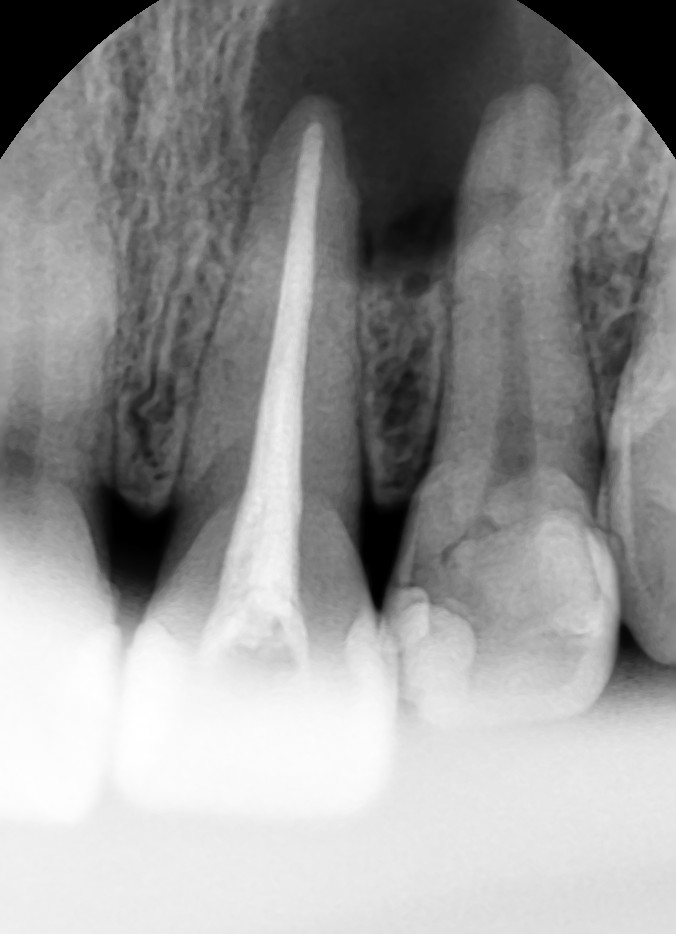

2013-07-26 PA 수술 후

치근단 수술 후 찍은 작은 사진입니다. 치아 뿌리 밑에 있던 염증조직을 긁어내고 뼈이식이 잘 되었음을 확인할 수 있습니다.